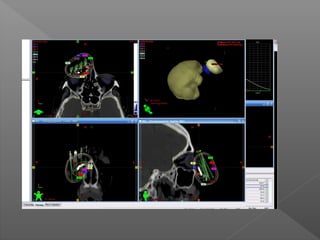

Definiciones:

1. Volumen macroscópico del tumor (GTV): volumen

perceptible por cualquiera de las imágenes o la

observación clínica.

2. Volumen Clínico de tratamiento(CTV): GTV + la

extensión microscópica del tumor.

3. PTV: expansión del CTV para compensar la

incertidumbre geométrica debido a la variación

de configuración y el movimiento de órganos